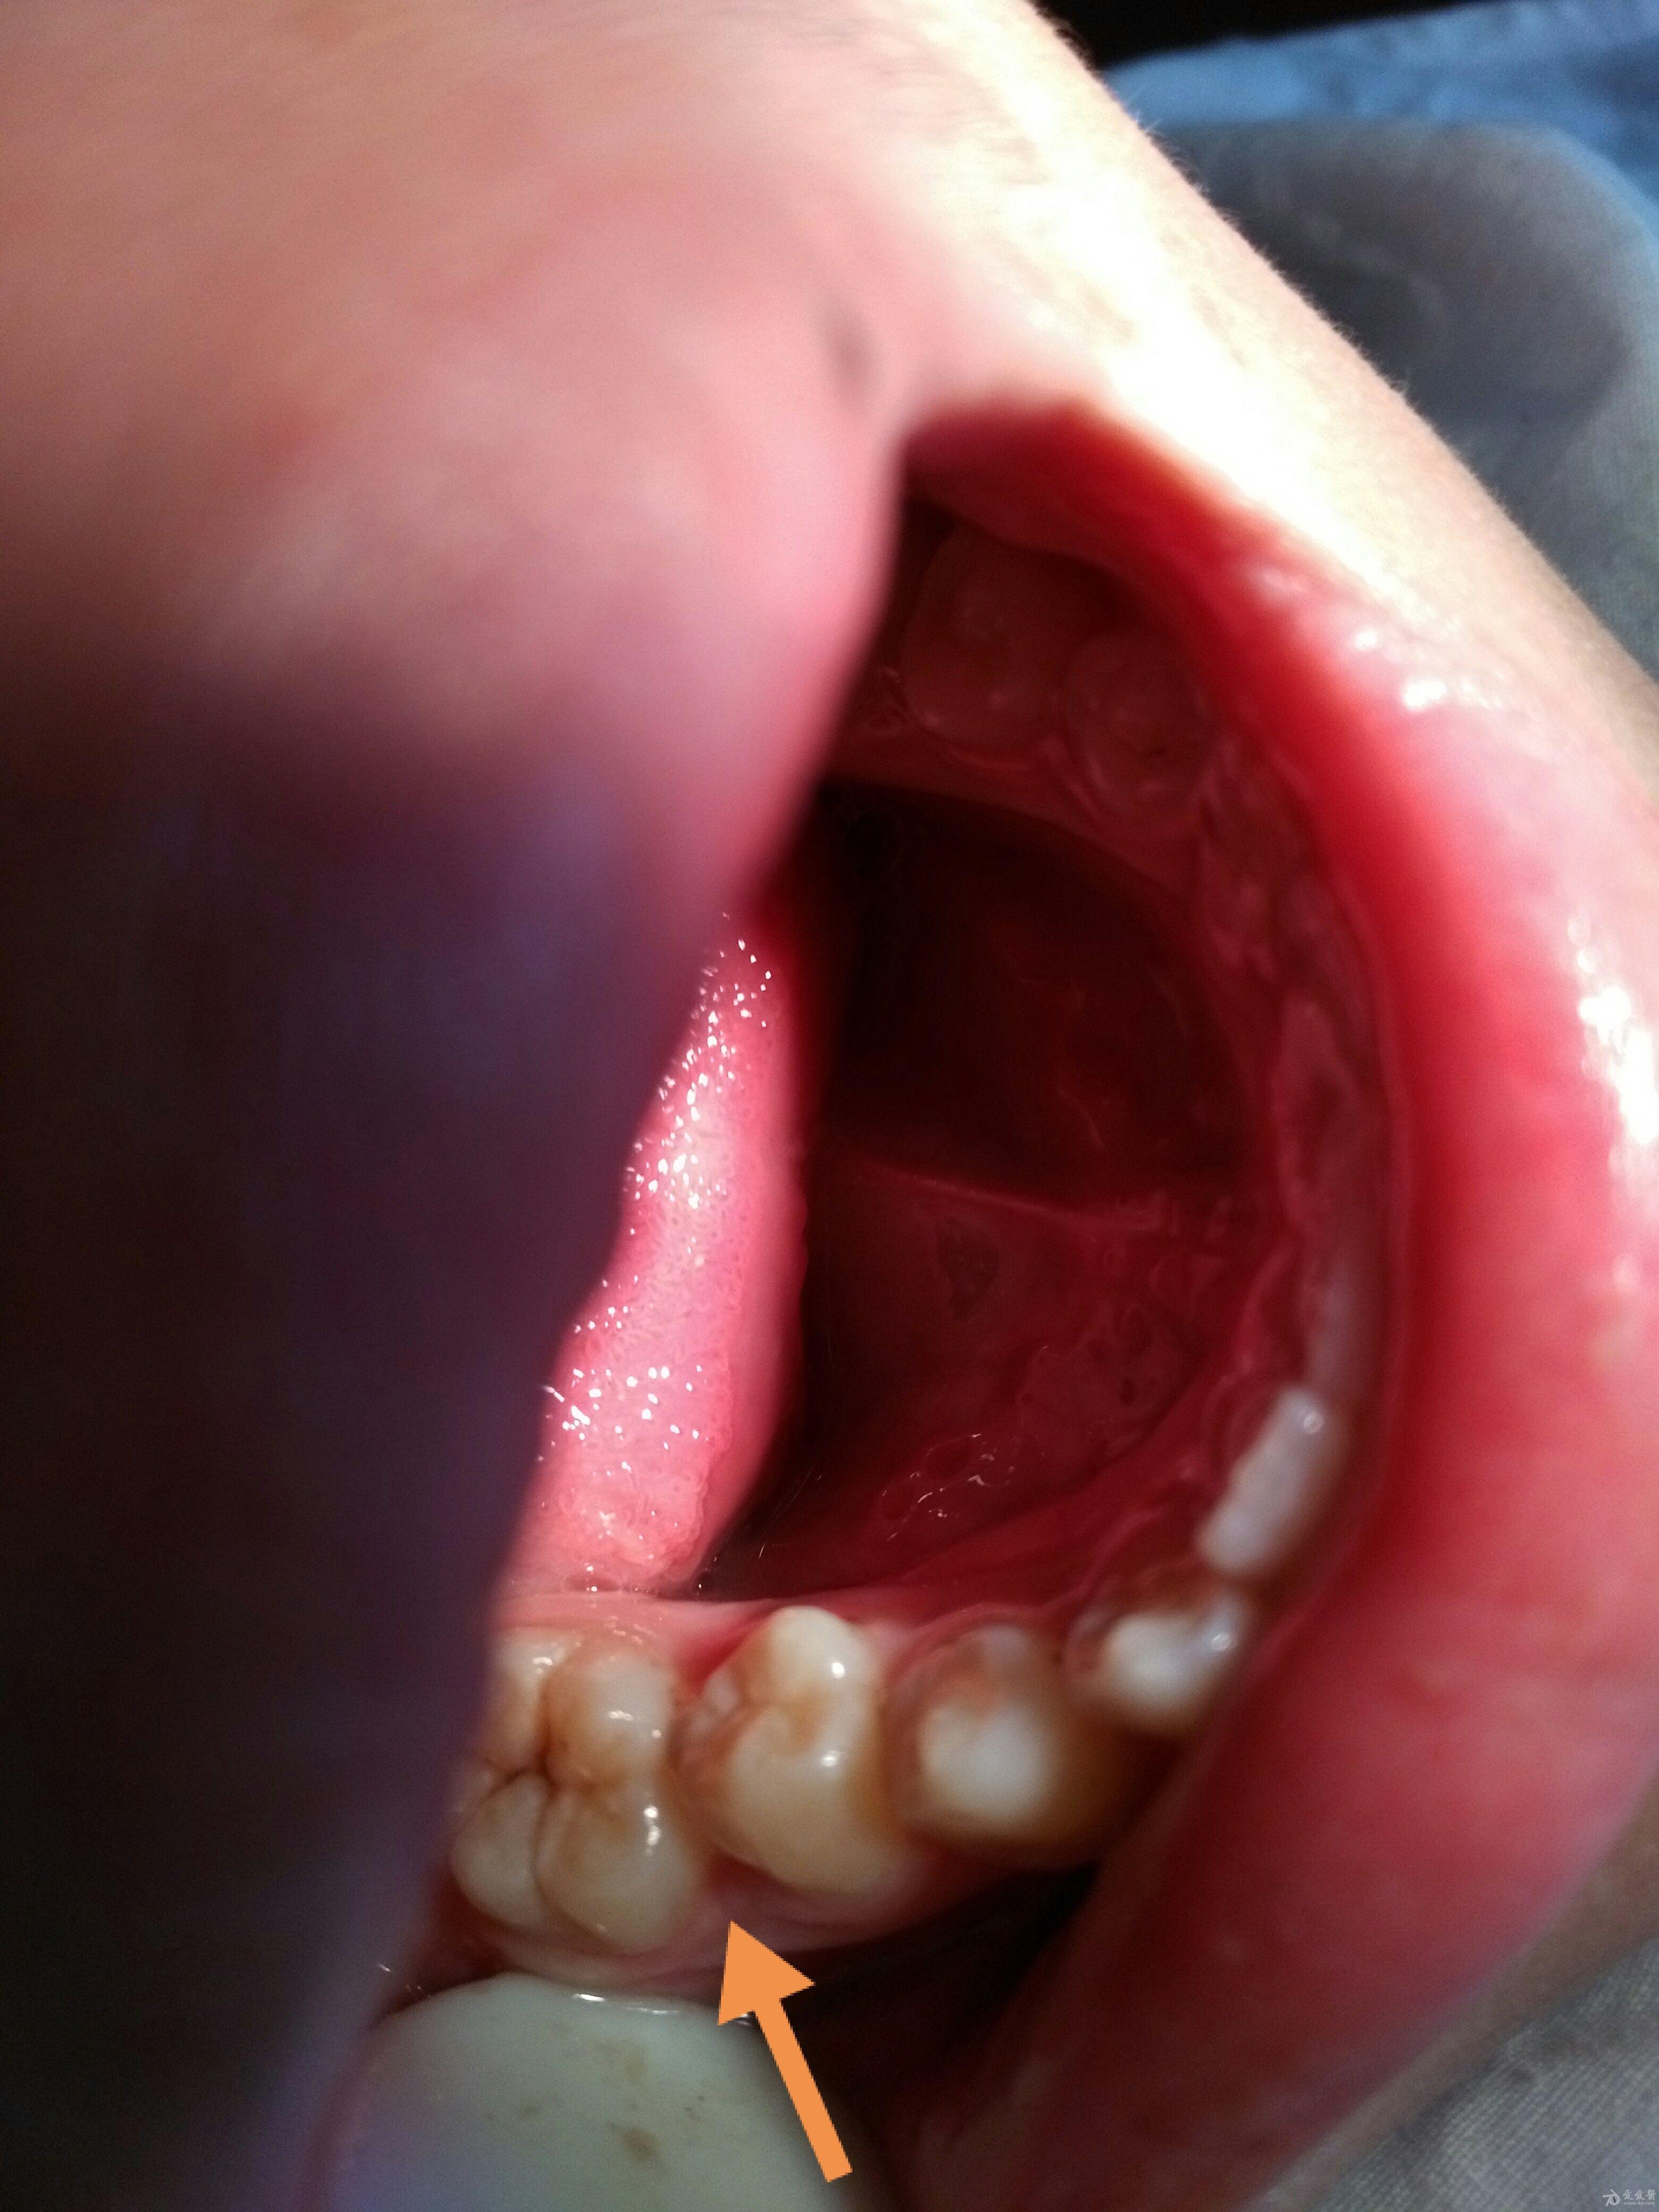

食物嵌塞如何处理

图片尺寸3120x4160